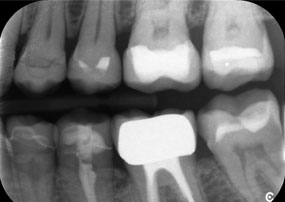

Предизвикателството беше да се премахнат дванадесет блок корони, изработени от сплав от неблагородни метали, без да се повредят подлежащите опорни зъби. Наконечникът беше използван за прецизно разрязване на керамичните слоеве и разделяне на металната конструкция с помощта на карбиден борер, което позволи минимално травматично отстраняване на короните. Само за 30 минути старите възстановявания бяха отстранени, което позволи подготовката на нова протеза, състояща се от циркониеви корони с пълна анатомична форма в задната част и фасети във фронталната зона. Резултатът беше цялостна реставрация, която осигури както функционален, така и естетичен успех (виж фиг. 1).